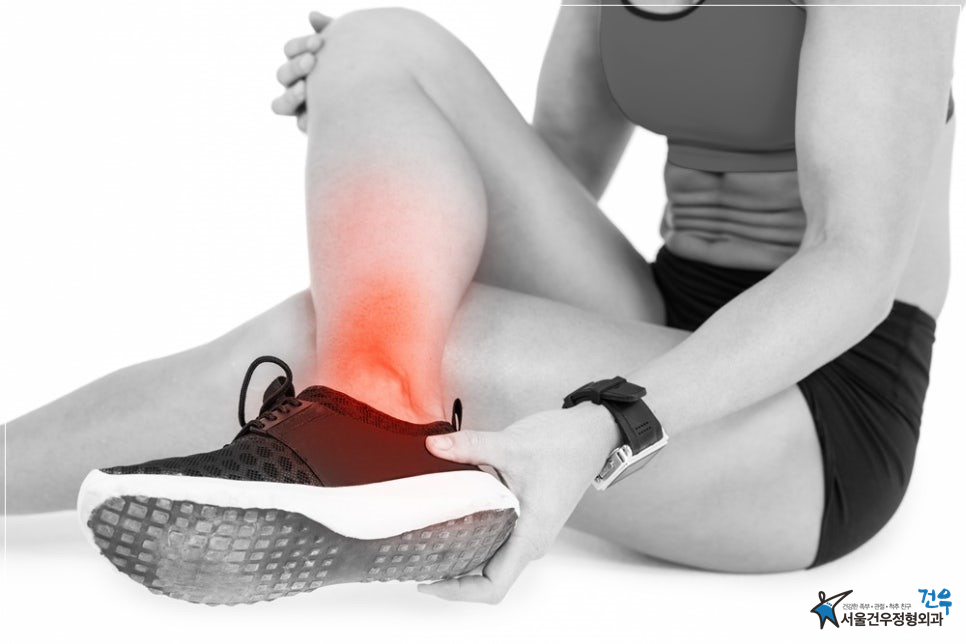

발목이 붓는 이유, 원인 및 거골 골연골병변에 대한 증상과 통증

발목이 붓는 것은 다양한 이유로 발생할 수 있습니다. 주로 거골 골연골병변과 관련이 있으며, 이로 인해 발생하는 증상은 다르다고 합니다. 이 글에서는 발목이 붓는 원인과 거골 골연골병변에 대한 증상과 통증에 대해 알아보겠습니다.

발목이 붓는다면 어떤 증상이 나타날까요?

거골 골연골병변으로 인해 발목이 붓는 경우, 다양한 증상이 나타날 수 있습니다. 주요 증상으로는 통증, 부종, 감각 이상, 운동 제한 등이 있습니다. 발목 부위가 붓고 뭉친 느낌이 들며, 보통 무리한 운동을 한 후 발생하는 경우가 많습니다.

발목이 붓는 주요 원인은 무엇인가요?

발목이 붓는 주요 원인은 거골 골연골병변으로 인한 것이 많습니다. 이 외에도 스포츠 부상, 관절염, 근육 부상, 만성적인 스트레스 등이 발목 부종의 원인이 될 수 있습니다. 발목이 지속적으로 붓거나 통증이 심해진다면 전문가의 진료를 받는 것이 중요합니다.